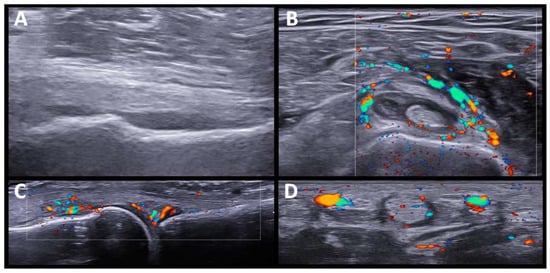

The US findings in RA-like patients were synovitis and tenosynovitis of the wrists and flexor tendon of the fingers. One patient also had synovitis in the knees and ankles, without involvement of the feet. Although they were seronegative (RF and anti-CCP), patients presented significant SH and PD signals, except for one patient treated with high doses of prednisone (40 mg/d). A set of US images with the most representative changes are shown in (Figure 1).

In our case series, US was performed after clinical assessment and as complementary information after physical examination. The US findings in patients with RA-like syndrome consisted of marked synovitis/tenosynovitis, although they were seronegative (anti-RF and ant-CCP), and presented high grades of SH and PD signals, with sonographic findings indistinguishable from typical RA. These US findings do not differ from those found in other series of patients with synovitis/tenosynovitis induced by ICI and studied by US [23].

Figure 1. US findings in RA-like pattern. (A,B). Carpal joint with synovial hypertrophy grade 2 and power doppler signal grade 2. (C). Knee suprapatellar recess shows synovial hypertrophy grade 3, and Power Doppler signal grade 2. (D,E). Tibiotalar, subtalar and tarsal joints with moderate synovitis and Power Doppler signal grade 2.